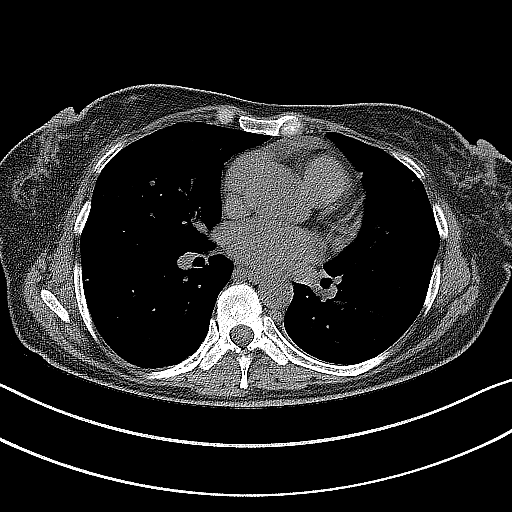

Image Grid

4×3 grid: Rows show different image types (Original NATIVE, Reconstructed NATIVE, Original VENOUS, Generated VENOUS), Columns show windowing techniques (No Window, Lung Window, Mediastinum Window)

Original VENOUS CT scan

No window - Raw intensity values

Original VENOUS CT scan

Lung window (WL -600, WW 1500 → Low −1350, High +150)

Original VENOUS CT scan

Mediastinum window (WL 40, WW 400 → Low −160, High +240)